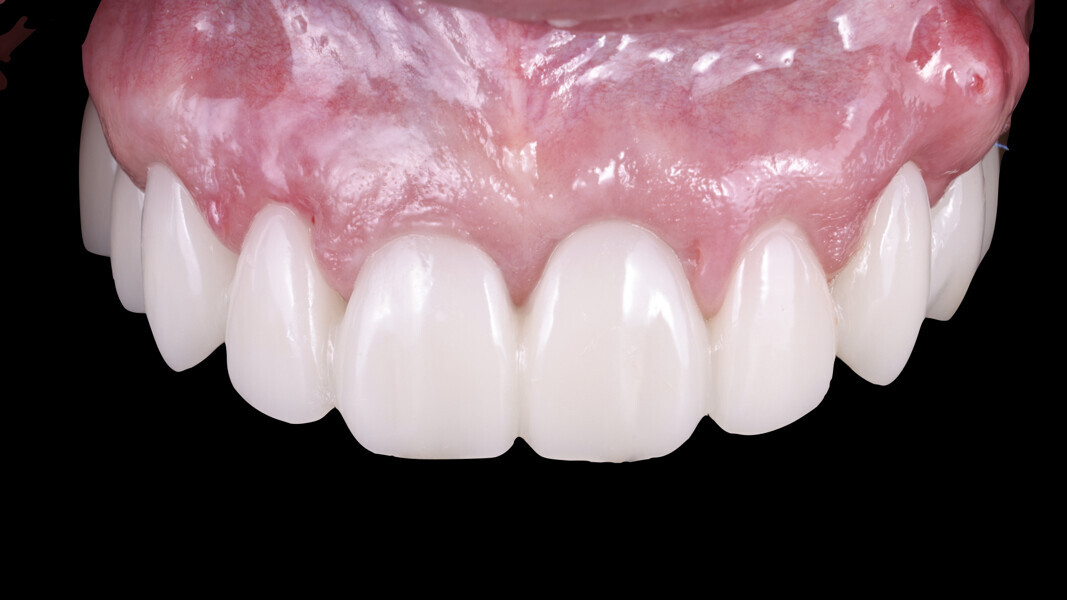

Restoration design

We begin with facial analysis and use planning software to select the appropriate tooth forms that complement the patient’s facial structure and determine the optimal apico-coronal tooth positioning. This step is particularly beneficial when the software allows us to modify tooth forms in relation to the patient’s soft-tissue contours, including papillary height, ideal gingival zeniths and other critical aesthetic parameters (Fig. 5). For this patient, as we aimed to achieve high papillae and have an excess of soft tissue to manipulate, we opted for trapezoidal tooth forms or potentially triangular forms rather than square ones. Once the desired tooth forms are selected, they are exported to a 3D CAD software program for precise positioning in the buccolingual dimension.

In this specific case, we strategically positioned the design palatally and more coronally. This compensated for the existing occlusal disharmonies while also shaping the soft tissue for prosthetically guided healing of the extraction sites. By integrating these adjustments, we could harmonise the patient’s bite and smile, achieving both function and aesthetics (Figs. 8–10).

Fig. 5: Facial analysis and smile design.